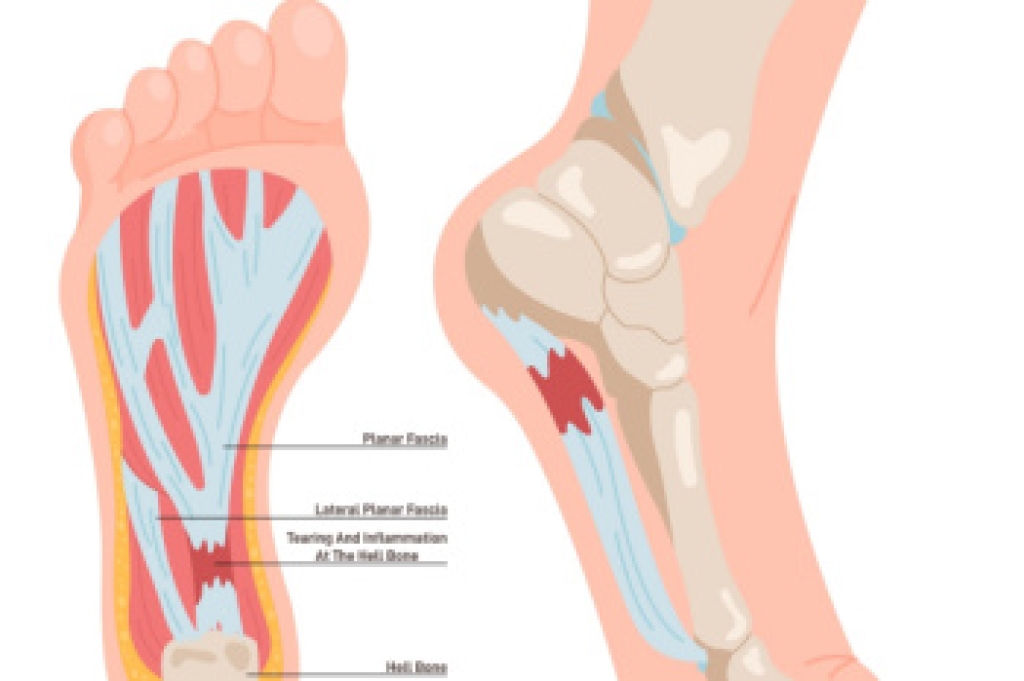

Pain in the arch of the foot can develop for several reasons, related to structure, strain, or injury. The arch is a curved area on the bottom of the foot that helps support body weight and absorb shock when walking. A frequent cause of pain in the arches is plantar fasciitis. This condition involves inflammation of a thick band of tissue that connects the heel to the toes. Flat feet or very high arches can also change how weight is distributed, placing extra stress on the arch. Overuse from prolonged standing, walking, or sports can strain muscles and ligaments. Injuries like sprains or small fractures may also lead to arch pain. A podiatrist can perform an exam and order imaging to confirm the cause. They also can provide orthotics, bracing, or suggested exercises to reduce strain and improve function. If you are experiencing foot arch pain, it is suggested that you make an appointment with a podiatrist for help.

To figure out the cause of foot pain, podiatrists utilize several different methods. This can range from simple visual inspections and sensation tests to X-rays and MRI scans. Prior medical history, family medical history, and any recent physical traumatic events will all be taken into consideration for a proper diagnosis.